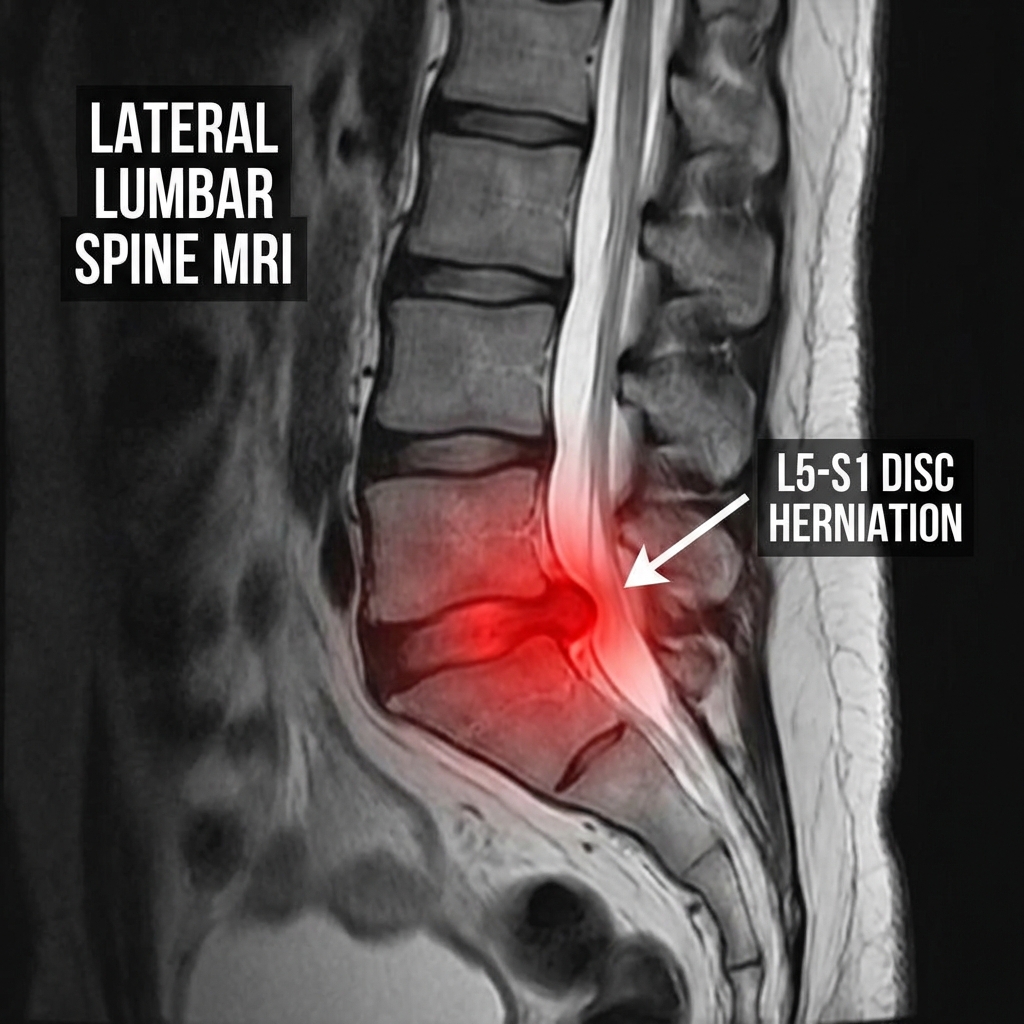

Maybe you've been diagnosed with a herniated disc, degenerative disc disease, or sciatica. Your doctor has likely presented surgery as an option, leaving you wondering if there's any other way forward.

Here's the frustrating truth about spinal conditions: they rarely improve on their own. The discs in your spine act as cushions between your vertebrae. Over time, these discs can become compressed, bulge outward, or even rupture. When this happens, the disc material can press against your spinal nerves, causing: